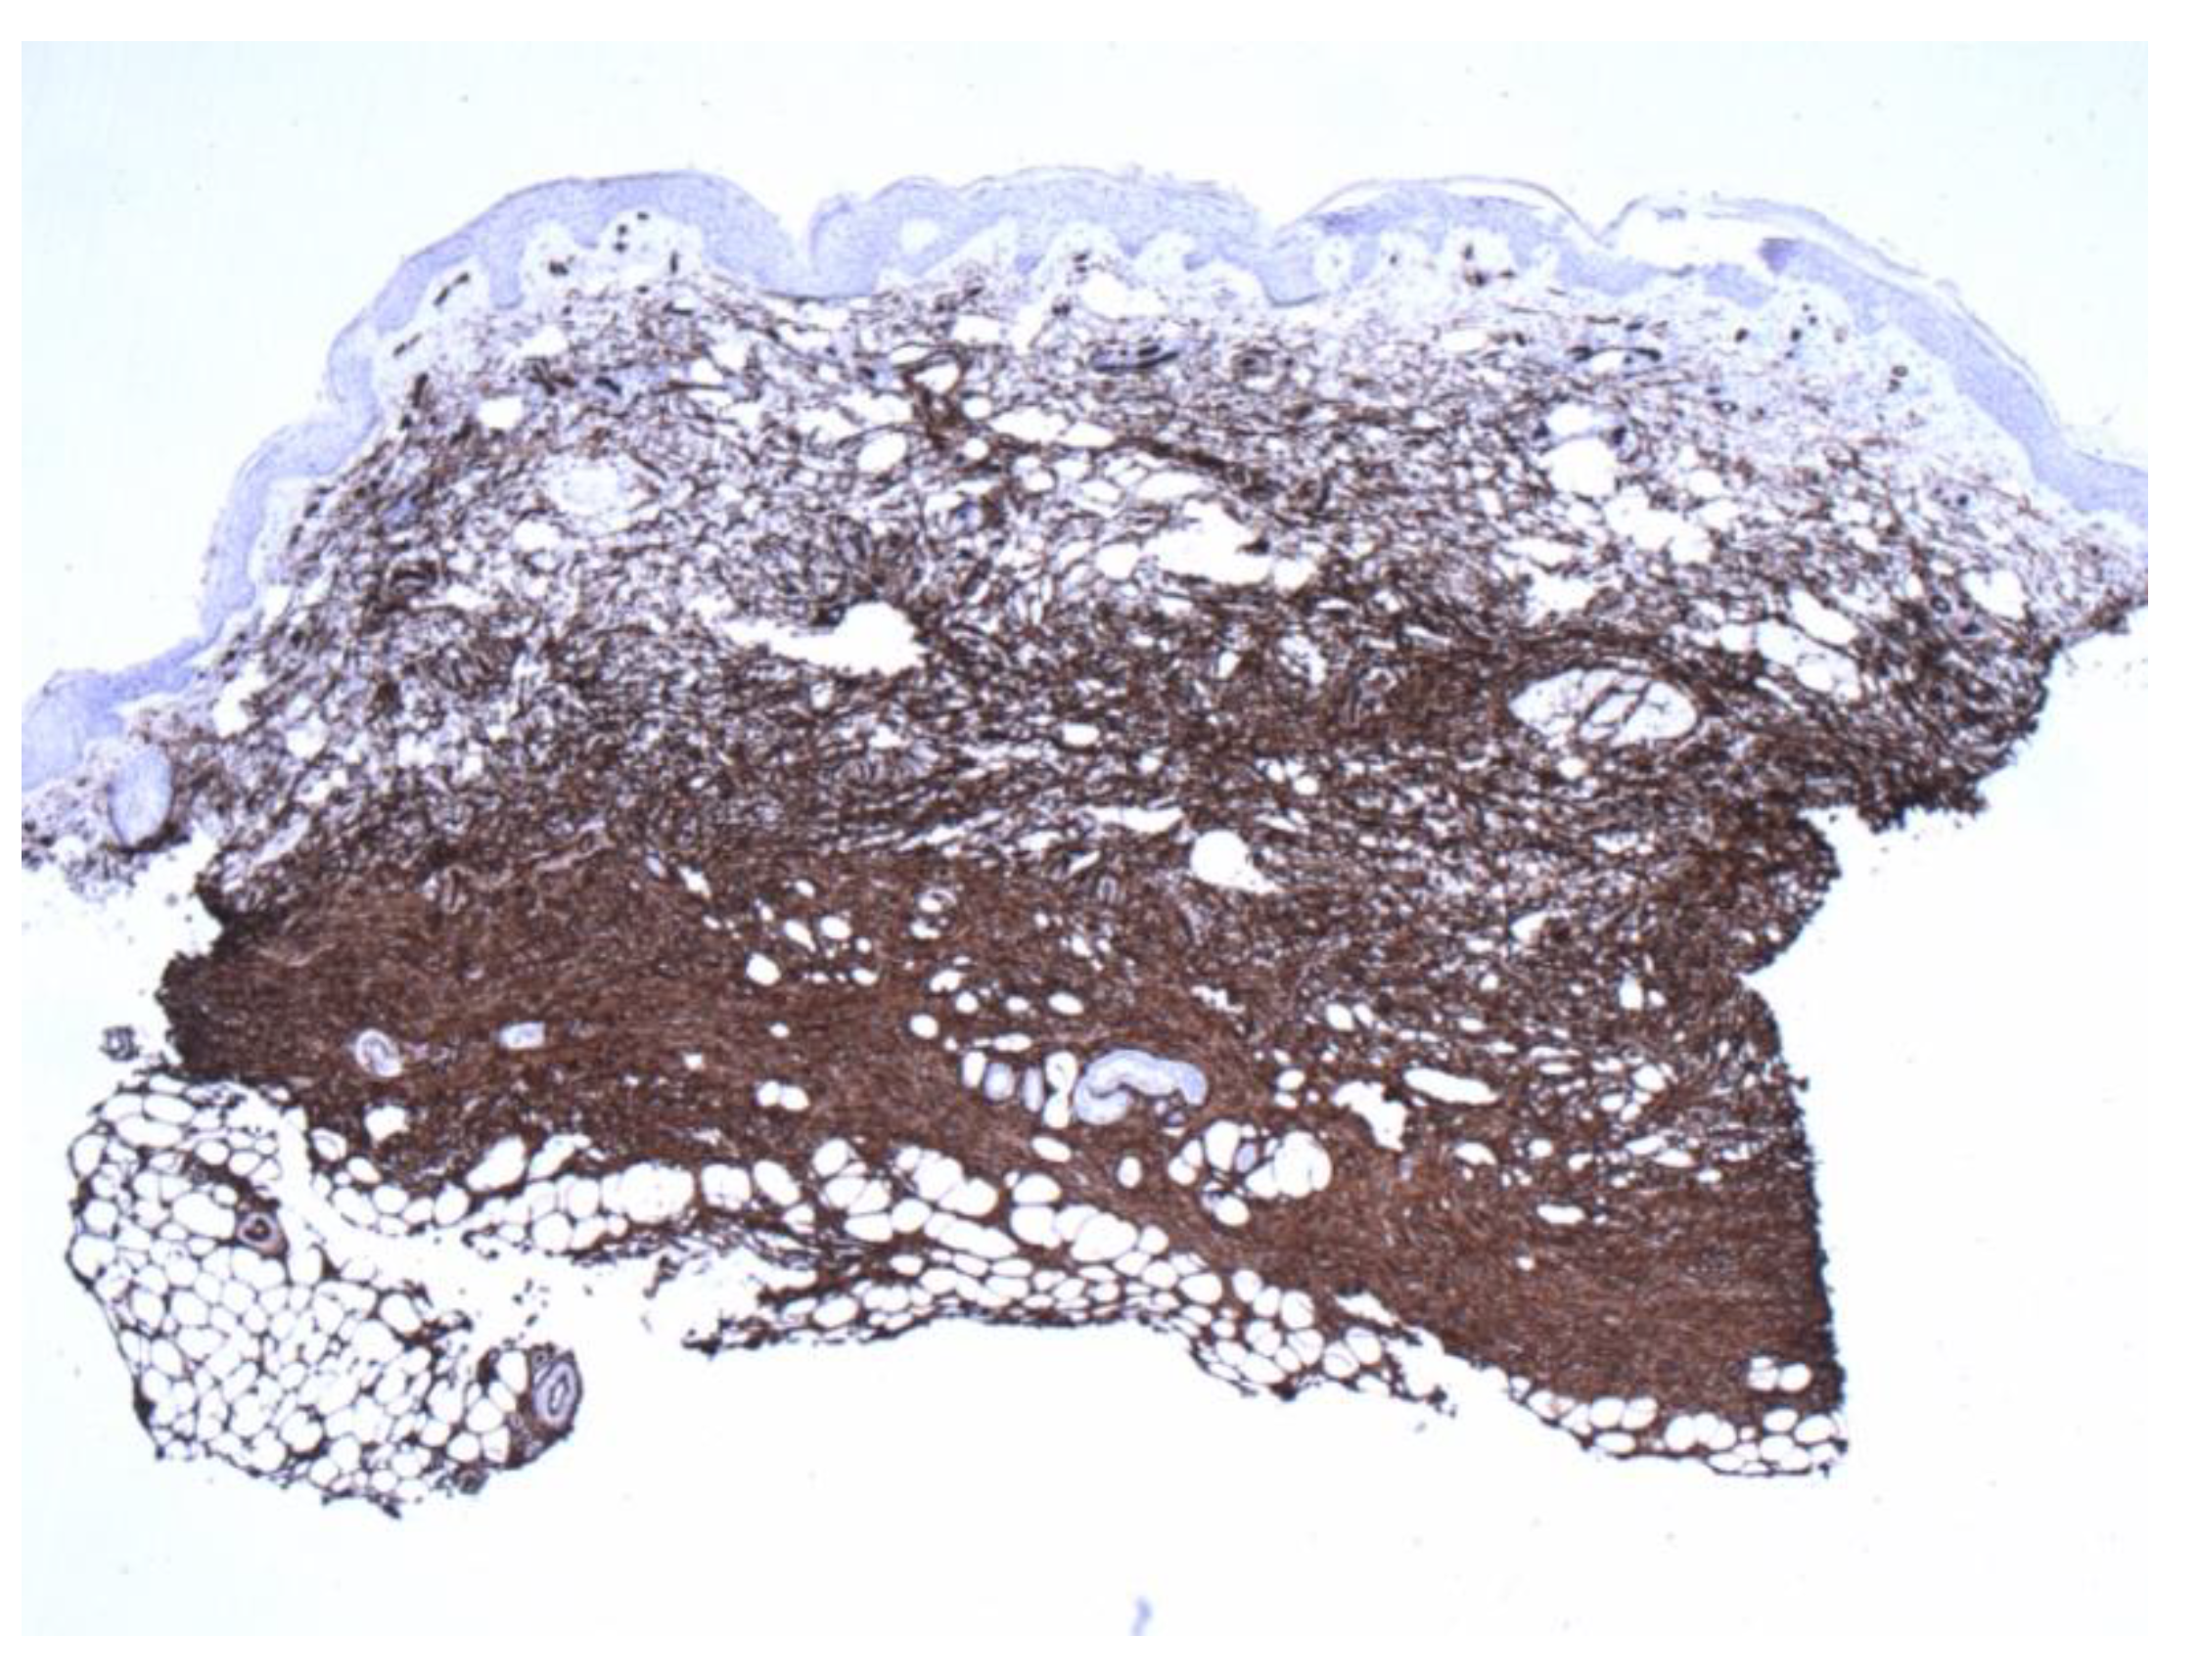

Figure 6.

Diffuse and even staining was also highlighted by CD34 preparation, compared with Figure 4. (4×).